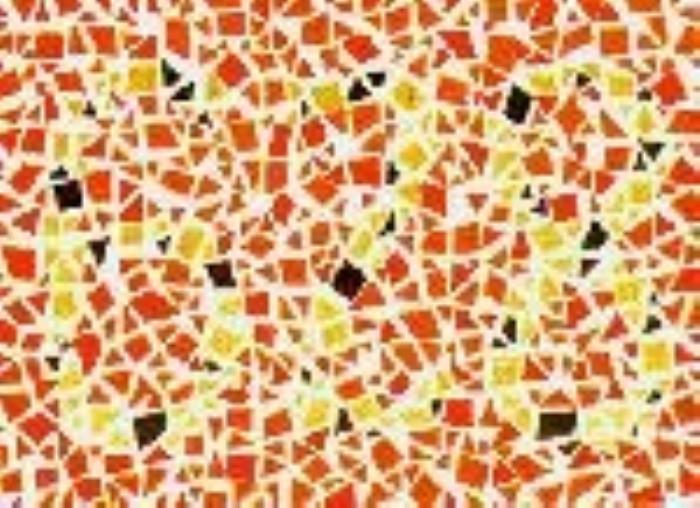

(正常 绿色盲 红色盲 蓝黄色盲)

(正常 绿色盲 红色盲 蓝黄色盲)

根据不同类型的色盲,以及色盲的严重程度,患者多少是能看到一些颜色的,或者说只是有些颜色看起来跟常人不同,但并不等于是“黑白”的世界。